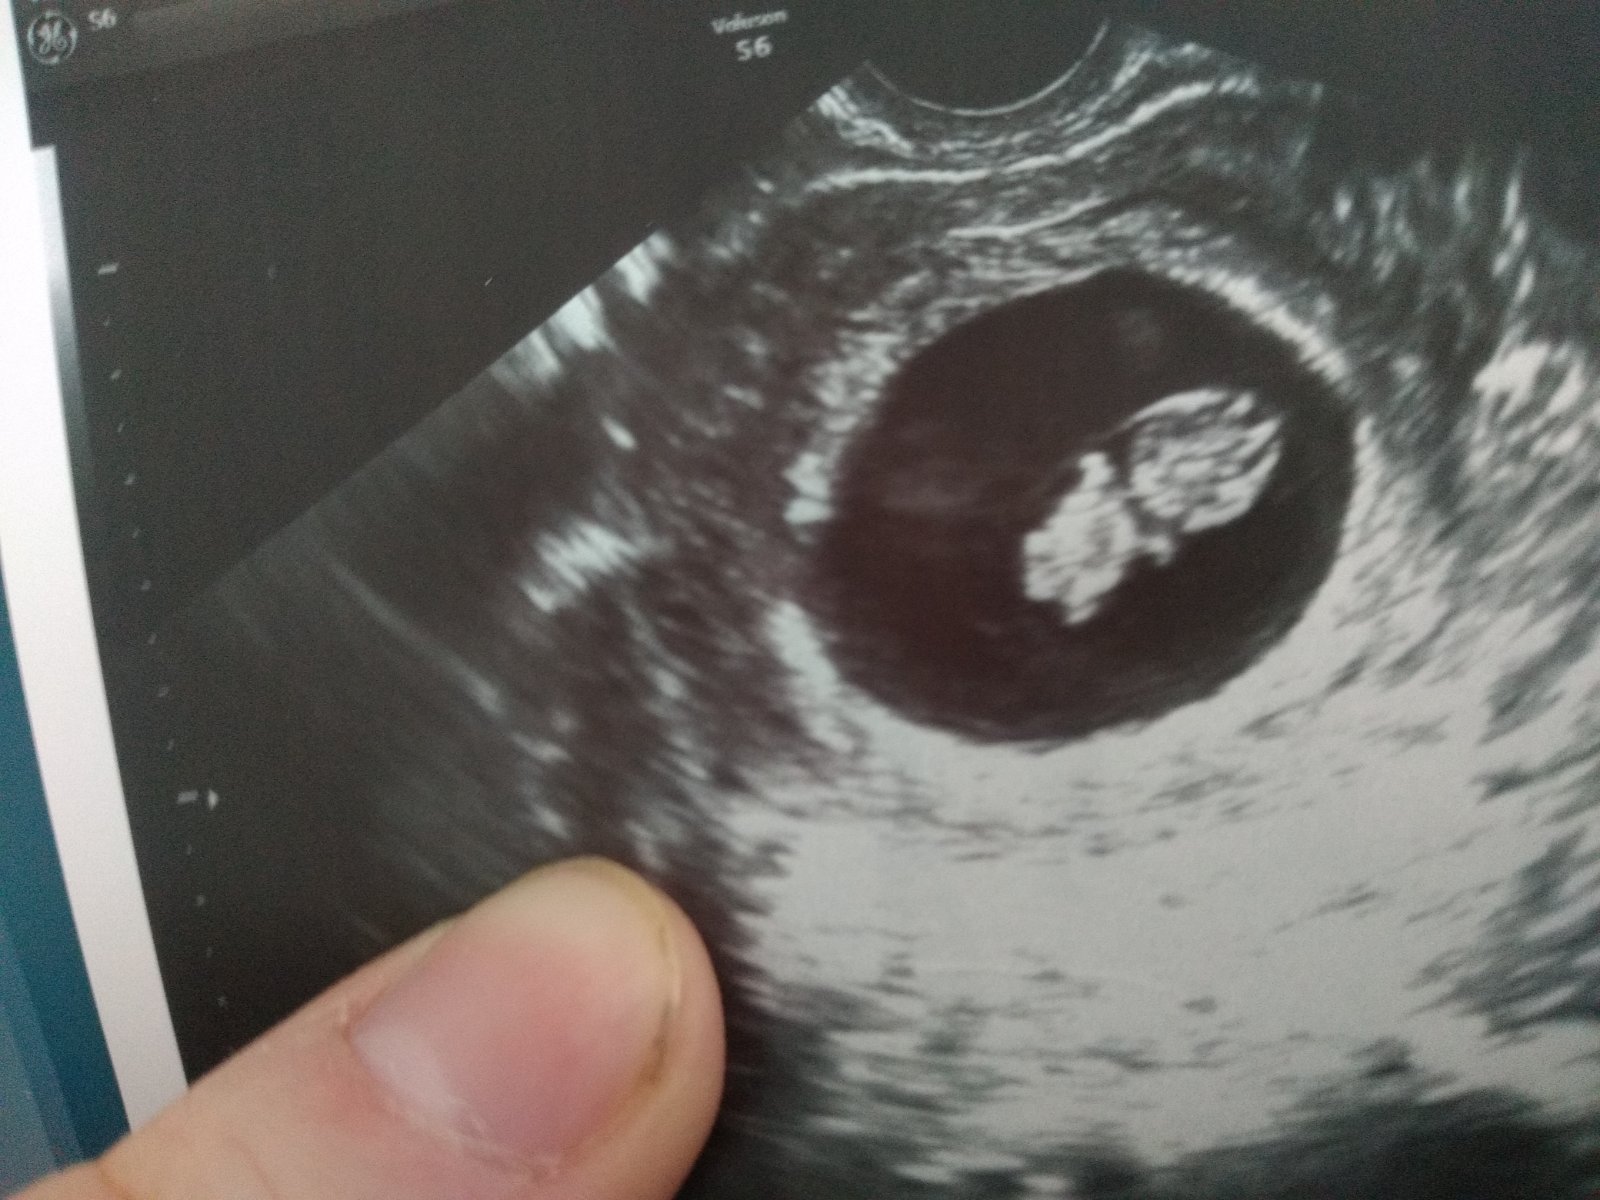

Ahojky holky,ráda se k vám přidám. Všechny vás tady moc zdravím 😊...Čekáme druhé dítě 🙏 máme doma 2,5 letého syna... Syn jen z ivf a těhotná jsem taky teď po ivf. Takže je to pro nás takový dar ❤️ včera jsem měla screening,dle ultrazvuku vše v pořádku 🙏 teď už jen čekat 14 dní na výsledky krve. Pokud prý nikdo nezavolá je vše v pořádku...tak se modlím. Čekání je strašné....Jinak dneska jsem 12+1...termín porodu 13.6.2023...a co vy holky ? Už po screeningu? Všem držím palce ať dopadne vše dobře 🙏❤️❤️